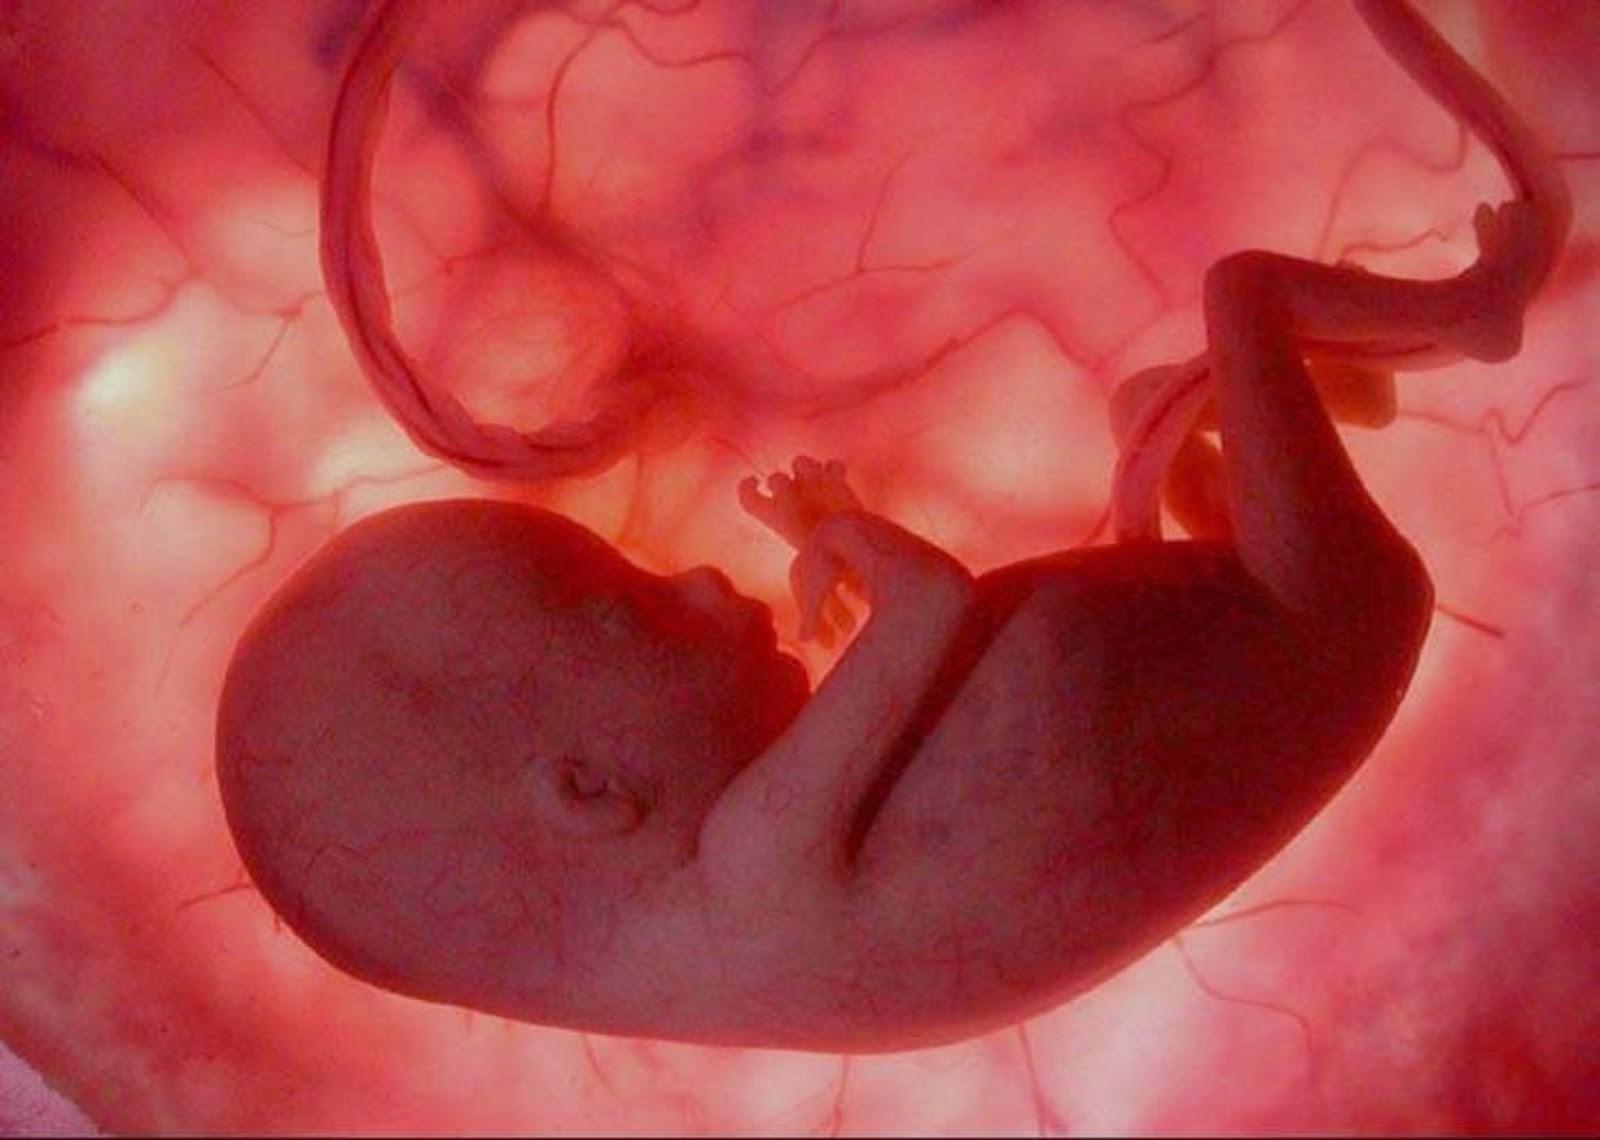

Эмбрион Леннарт Нильсон

Эмбрион Леннарт Нильсон

Эмбрион Леннарт Нильсон

Леннарт Нильсон снимки в утробе